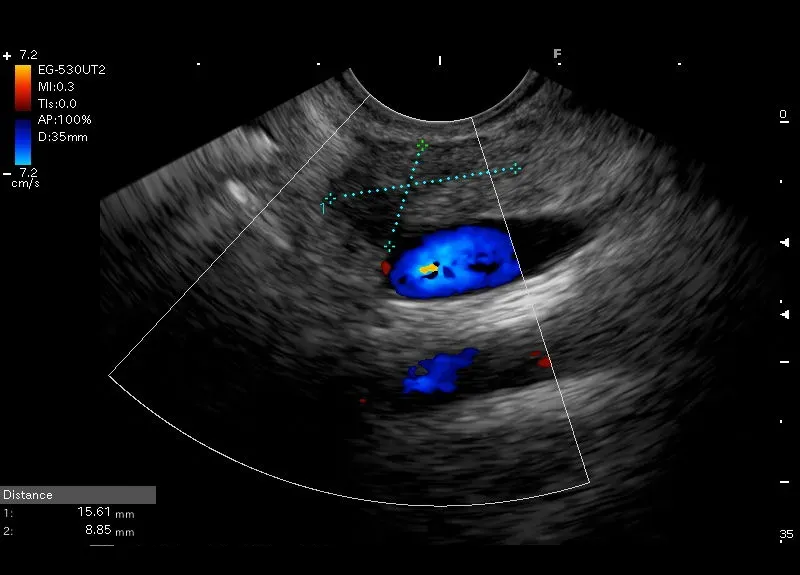

Stan po ostrym, zapaleniu trzustki u dziewczynki 17 letniej.

W trzonie obszar o niejednorodnie obniżonej echogeniczności wielkości około 16x9mm, bez komunikacji z przewodem Wirsunga i bez widocznego przepływu w opcji power doppler, odpowiadający najprawdopodobniej zmianom pozapalnym.